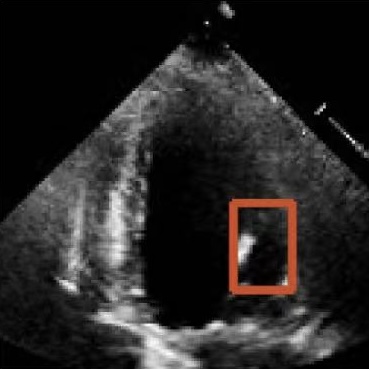

Challenges in Echocardiography Segmentation 超声心动图视频分割面临的挑战

Echocardiography segmentation faces several challenges such as low contrast, speckle noise, and signal dropout. 超声心动图视频分割面临着诸如低对比度、斑点噪声和信号丢失等多重挑战。

Noise

(a)

Blur

(b)

Figure 2. Illustrative challenges for echocardiography video segmentation: (a) speckle noise, (b) indistinct or blurred contours, and (c-f) the substantial changes in the target’s shape and scale throughout the cardiac cycle. 图 2. 超声心动图视频分割面临的典型挑战:(a) 斑点噪声,(b) 轮廓不清或模糊,以及 (c-f) 在整个心动周期中目标的形状和尺度发生的显著变化。